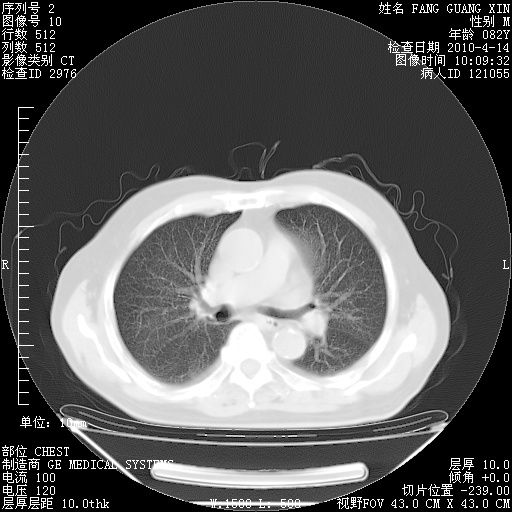

4月14日肺部CT